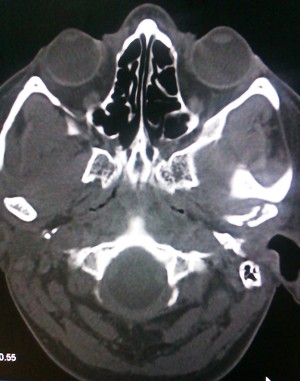

Case 1: A 40-year-old female patient reported to the department of dentistry, with the chief complaint of pain during mastication in the left preauricular region. There was a history of fall from bike one week before. There was no pain or swelling present initially, but she developed pain after one week of trauma which subsided by medication. No history of ear bleed was reported. On palpation, head of the condyle was present in the glenoid fossa, with diminished movements on the left side. In the OPG no fracture was visible. The initial diagnosis of traumatic arthritis was made, and the patient has advised a soft diet and moist heat application. Though the intensity of pain reduced after 2 weeks,it persisted,hence theC.T scan was advised. Computed tomography revealed bony changes in the fractured mandibular condyle and its position in the mandibular fossa more precisely than conventional radiographic examinations. In the axial section, there was a sagittal fracture of the left condyle. Intermaxillary fixation was done for two weeks.

Figure 1. Axial CT showing vertical fracture of left condyle of mandible.